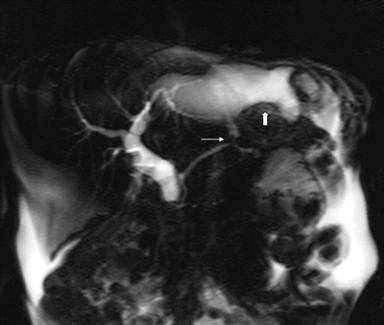

A 47-year-old female with a history of chronic alcoholic pancreatitis and remote subtotal gastrectomy with Roux-en-Y gastrojejunostomy was referred to for management of a pancreaticopleural fistula. The patient presented with worsening dyspnea. Thoracentesis of a large left pleural effusion was done showing a markedly elevated amylase (138.000 IU/L). MRI revealed a pancreatic pseudocyst with a pancreaticopleural fistula (Figure 1). The patient required daily therapeutic thoracentesis because of a shortness of breath.

Figure 1. MRI showing a leak from the main pancreatic duct (narrow arrow) into fluid tracking superiorly toward the left pleural space (wide arrow). |